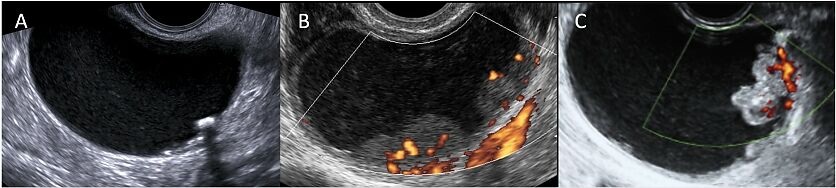

The high rate of spontaneous resolution highlights the suitability of conservative management, consistent with previous studies showing that decidualization typically resolves postpartum, thereby reducing the need for immediate intervention21 (Figure 1).

Transvaginal ultrasound images (color Doppler and B-mode) of a known endometrioma at different gestational ages: (A) 12 weeks of gestation; (B) 24 weeks of gestation; (C) 37 weeks of gestation; (D) postpartum. The color Doppler images (A–C) show a unilocular solid cyst with ‘ground-glass’ content, regular external margins and irregular internal margins due to the presence of a vascularized papillary projection. The vascularization of the papilla increases during early pregnancy, reaching a peak at 24 weeks, and then decreases in the third trimester. The papilla maintains a smooth and regular contour throughout gestation. The postpartum scan (D) shows resolution of the papillary structure and reappearance of the typical endometrioma features. This case illustrates a transient, pregnancy-related vascularized papillary projection within an endometrioma, which spontaneously regressed after delivery.

Decidualization of endometriomas is a benign, temporary and dynamic process unique to pregnancy, distinguishing it from the irreversible neoplastic changes associated with malignancy. However, further research is needed to better characterize this phenomenon and improve the ability to differentiate benign decidualization from true malignancy.